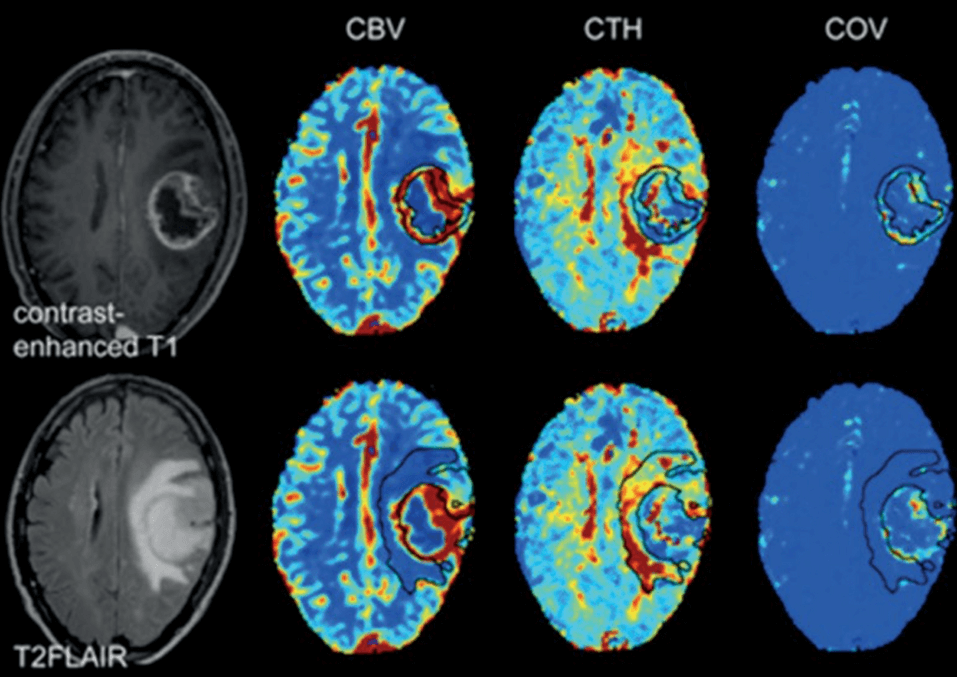

ONCOLOGIA- Imaging Metabolico e Perfusionale Avanzato

Nelle patologie oncologiche cerebrali, una caratterizzazione accurata della lesione è essenziale per stabilire aggressività, trattamento e prognosi.

Le sfide dell’imaging oncologico

- Difficoltà nel distinguere progressione tumorale da pseudoprogressione.

- Necessità di una valutazione combinata vascolare + metabolica.

- Parametri tradizionali spesso insufficienti.

BIOMARCATORI PROPRIETARI PER LA NEURO-ONCOLOGIA

Biomarcatori Vascolari

- CTH Eterogeneità del tempo di transito capillare.

- COV Coefficiente di varianza microvascolare.

- Leakage Integrità della barriera emato-encefalica.